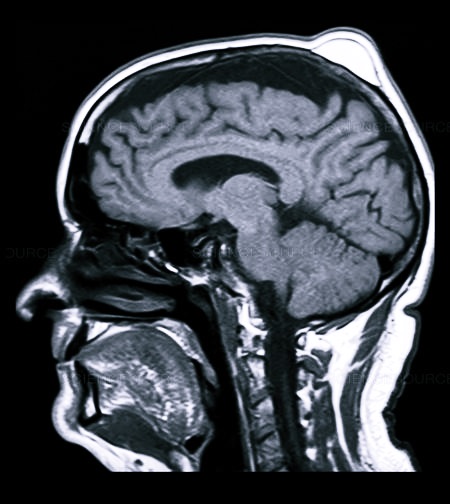

На голове проводится и УЗИ исследование, помогающее определить видоизменения в тканях и костных структурах, иногда МРТ, в виде дополнительной меры диагностики.

- МРТ или КТ;